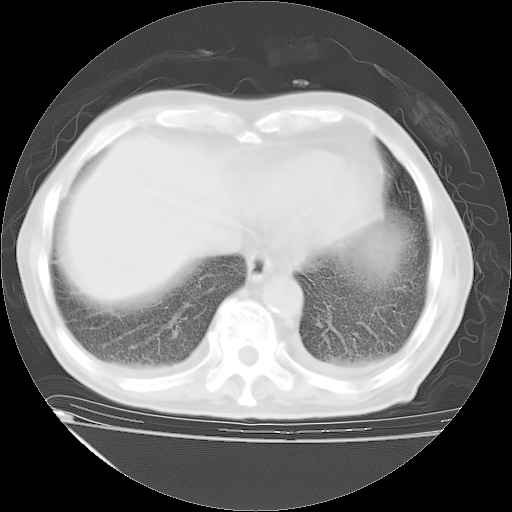

经过24天治疗,岳父的病情基本稳定。生活基本可以自理,可以下床活动。呼吸困难早已消失。体温基本正常。

主要治疗甲强龙80mg×14天,60mg×10天;同时抗结核(异烟肼+利福平+乙胺丁醇)。环磷酰胺0.1 tid 10天。

特别感谢胡教授、高管、桃子版主给出关键的治疗建议。桃版把所有肺部影像和全部临床资料请所在医院呼吸科、感染病科、结核科、临床免疫科专家会诊。临床免疫科专家制定了完整的治疗方案。